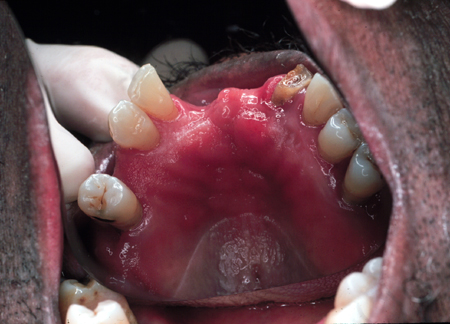

Candidíase oral

Infecção por candidíase pseudomembranosa em um paciente portador do vírus da imunodeficiência humana (HIV)

Public Health Image Library (PHIL)